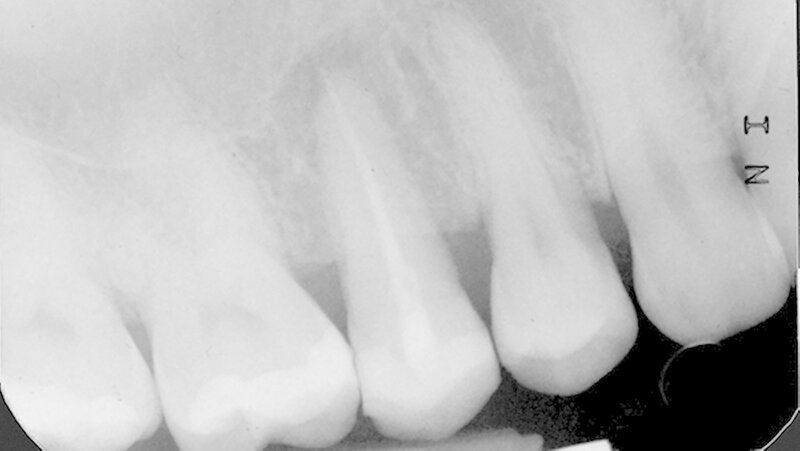

In der Poliklinik für Zahnerhaltung des Universitätsklinikums Münster war zwar die allgemeinmedizinische Anamnese unauffällig, doch zeigte sich klinisch nach Entfernung der vorhandenen mod-Glasionomerzementfüllung ein deutlicher Frakturspalt in mesial-distaler Ausrichtung am Boden der Kavität (Abbildung 1). Darüber hinaus war auf der Röntgenaufnahme des Vorbehandlers eine apikale Aufhellung zu erkennen (Abbildung 2).